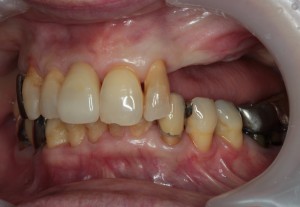

症例⑤

上左右の奥歯を失ってしまったため、保険の入れ歯を入れたが、違和感が強く、しっかり噛むことができないため、インプラントを併用した入れ歯を作ることで違和感なく、しっかり噛むことができるようになった。 また通常の入れ歯は、はずれないようにするため金属のバネを歯に引っ掛けるため見た目も悪いが、インプラントによって固定されているためバネもなく、見た目も非常に良いものとなっている。

術前

術前レントゲン写真

術後レントゲン写真